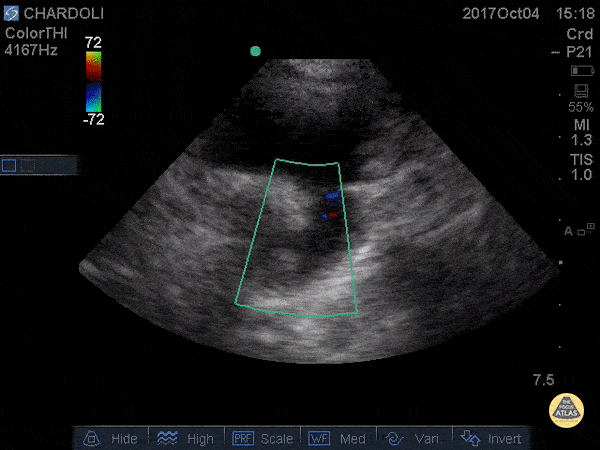

WCUME 2017 submission for "Best POCUS" 8 y/o M with undifferentiated dyspnea. POCUS reveals he has open PDA on aorta from suprasternal view. Dr. Nima Shekar Riz Fomani - Firoozgar General Hospital